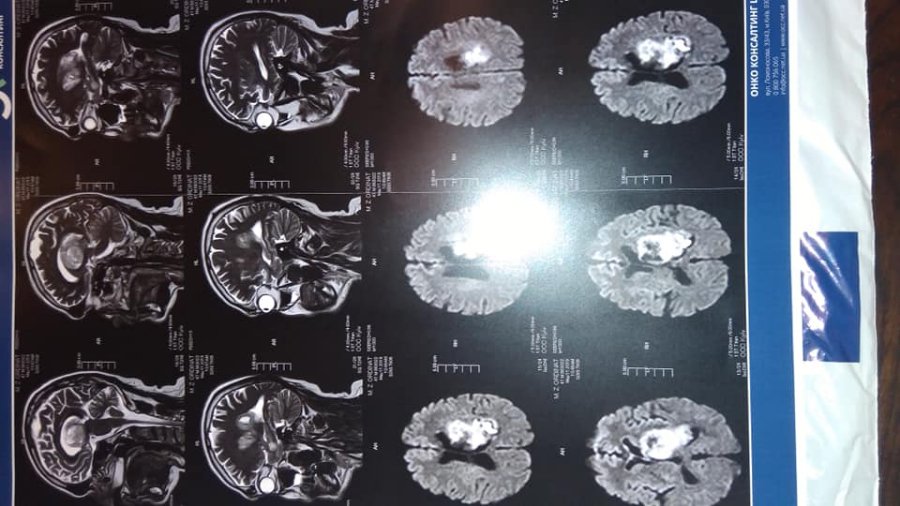

У чоловіка медсестри Волинського обласного госпіталю ветеранів війни Тетяни Ордінат Миколи Ордіната виявили пухлину в голові. Тож родина звертається за допомогою до милосердних та небайдужих до чужого горя людей, аби врятувати чоловіка.

"Якщо відійти від медичної термінології то сказати можна просто і зрозуміло: хвороба прогресує, і душе швидко. Навіть звичайній людині зрозуміло, що білі плями на фотознімку, який нижче, – це щось зайве...

Попри все, є надія, що можна побороти захворювання, тож мусимо просити Вас допомогти назбирати на лікування необхідну суму грошей.